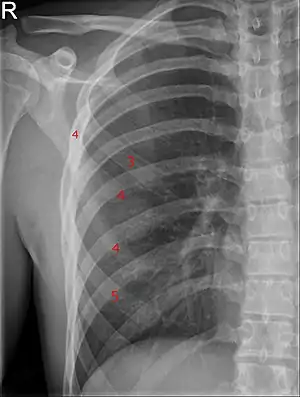

| Bifid rib at the right side seen on chest radiograph. The fourth rib splits in two towards the sternal end. | |

A bifid rib is a congenital abnormality of the rib cage and associated muscles and nerves which occurs in about 1.2% of humans. Bifid ribs occur in up to 8.4% of Samoans.[1] The sternal end of the rib is cleaved into two. It is usually unilateral.